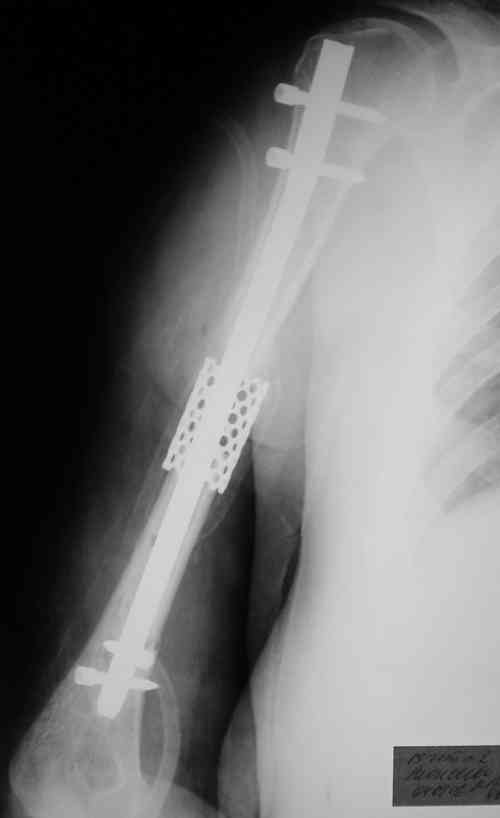

LCP Distal Humerus Plates

Такие надмыщелковые переломы в изолированном виде у нас в последние годы обычно фиксируются плоским титановым стержнем a la Зверев-Ключевский антеградно. Но тут еще и вышележащие проблемы.

Наверно, можно пойти на укорочение, убрав металлический цилиндр, не такой уж большой дефект. Снимки в чем-то похожего пациента прилагаю - тоже несращение диафиза после многократных операций, и надмыщелковый свежий перелом (случился после удаления обломка стержня аппарата).